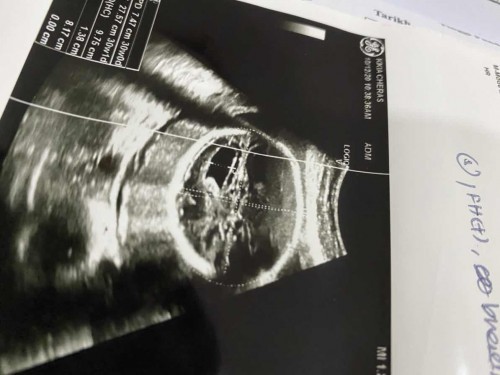

Hi momies. Nak tanya ada yg experience ventriculomagely sblm ni tak? tadi scan dkt kk cakap macam ada air dalam kepala baby. then dr suruh refer hospital. Tapi nak tunggu appoinntment dr seminggu lagi tapi hati ni dah resah sangat 😂 Haritu buat details scan dekst private takde cakap apa pun. okay ke semua. If ada momies yg pernah experience ni share share la ye